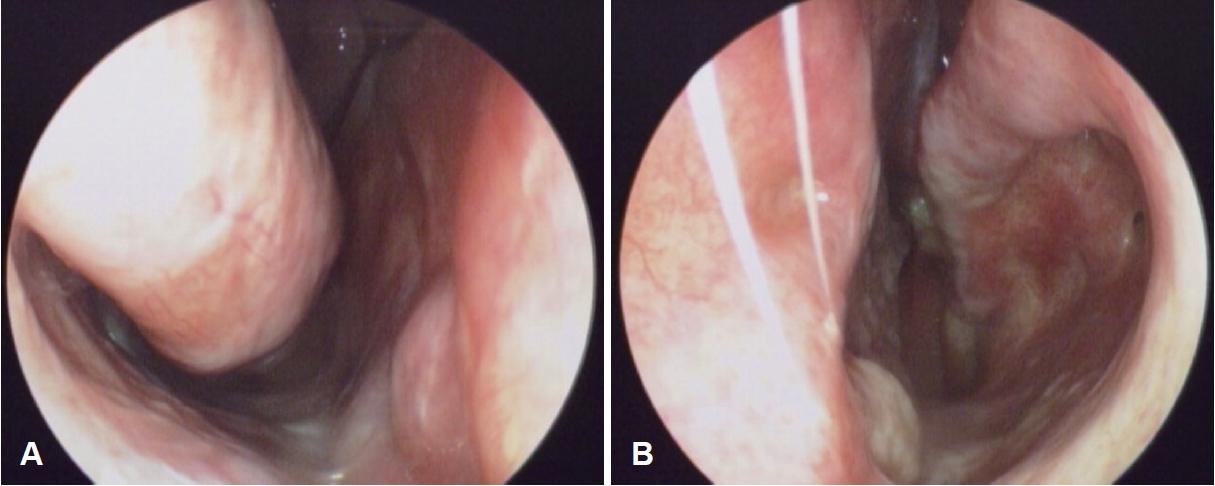

방 법수술 전 평가수술 전 평가과정에서 비내시경 검사를 통해 환측 하비갑개가 건측에 비해 심한 결손과 위축이 있는지 확인하고 정확한 문진을 통해 코 수술 과거력을 파악하였다(Fig. 1). 알레르기 검사, 후각검사를 시행하였으며 증상의 정도를 평가하기 위한 sino-nasal outcome test (SNOT-22) 설문지를 시행하였다. 전산화단층촬영(CT)을 통해서 환측 하비갑개가 건측에 비해 결손된 부분이 있는지, 다른 해부학적 이상이 없는지 다시 확인하였다(Fig. 2). 빈코 증후군의 진단에 도움이 되는 cotton test를 시행하였으며 생리식염수를 적신 솜을 비강 내에 넣어둔 상태에서 증상이 호전되는지 확인하였다.

NotesAuthor Contribution Conceptualization: Sang Jae Lee, Hyung Gyun Na. Data curation: Sang Jae Lee, Yoon Seok Choi. Formal analysis: Chang Hoon Bae, Hyung Gyun Na. Investigation: Yoon Seok Choi, Chang Hoon Bae. Methodology: Sang Jae Lee, Hyung Gyun Na. Project administration: Yong-Dae Kim, Chang Hoon Bae. Resources: Yong-Dae Kim, Si-Youn Song. Supervision: Hyung Gyun Na. Visualization: Sang Jae Lee, Si-Youn Song. Writing—original draft: Sang Jae Lee. Writing—review & editing: Sang Jae Lee, Hyung Gyun Na. Fig. 1.Pre operative nasal endoscopic view shows defect and atrophy at left inferior turbinate compared with right inferior turbinate. Right (A) and left (B). Fig. 2.Pre operative CT scan shows defect and atrophy at left inferior turbinate compared with right inferior turbinate. Axial (A) and coronal (B). Fig. 3.Inferior turbinate reconstruction procedures with autologous costal cartilage graft. Block insertion at left nasal floor (A), augmentation graft with diced and crushed costal cartilage mixed with glue (B), and intra operative nasal endoscopic view shows well-reconstructed and regular surface at left inferior turbinate (C). *indicates the location where the reconstruction was done. REFERENCES1. Chhabra N, Houser SM. The diagnosis and management of empty nose syndrome. Otolaryngol Clin North Am 2009;42(2):311-30, ix.